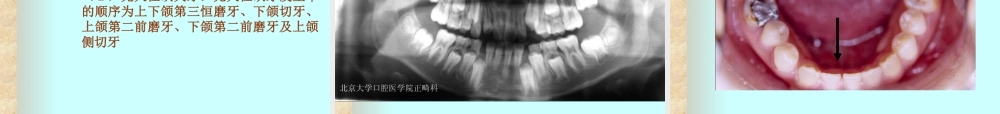

第三章错合畸形的病因北京大学口腔医学院正畸科错合畸形的病因掌握内容:口腔功能因素,口腔不良习惯导致错合畸形的临床表现及形成机制熟悉内容:替牙期常见局部障碍与错合畸形的关系错合畸形的病因一、遗传因素:来源于种族演化和个体发育二、环境因素:可分为先天因素和后天因素环境因素(一)先天因素1.母体因素2.胎儿因素3.常见的发育障碍及缺陷(1)额外牙:(2)先天性缺失牙:(3)牙大小形态异常:(4)舌形态异常:(5)唇系带异常:环境因素(二)后天因素1.某些急性及慢性疾病2.佝偻病3.内分泌功能异常4.营养不良环境因素(三)功能因素1.吮吸功能异常2.咀嚼功能异常3.呼吸功能异常4.异常吞咽5.肌功能异常环境因素(四)口腔不良习惯1.吮指习惯2.舌习惯3.唇习惯(1)咬下唇习惯:(2)咬上唇习惯:(3)覆盖下唇:4.偏侧咀嚼习惯多发生在乳牙后期5.咬物习惯6.睡眠习惯环境因素(五)乳牙期及替牙期的局部障碍1.乳牙早失2.乳牙滞留3.恒牙早失4.恒牙早萌5.恒牙萌出顺序紊乱6.多数乳磨牙早期缺失7.乳尖牙磨耗不足8.下沉乳牙(六)骨性错合的病因遗传环境因素一、遗传因素遗传因素:遗传基因决定。遗传(heredity)和变异(variation):错合畸形的遗传因素,来源于种族演化和个体发育。(一)种族演化错合畸形是随着人类的种族演化(raceevolution)而发生和发展的80万~50万年前的古人头骨上未发现错合10万年前尼安德特人头骨上有轻微错合殷墟人错合占28%而现代人类错合约占48.9%错合畸形的根本原因机制如下:1.原始人从爬行到直立2.咀嚼器官退化性缩小3.咀嚼器官的退化呈现出不平衡现象(二)个体发育在单卵双生子,遗传特性几乎完全相同双卵双生子则与寻常弟兄一样,具表现的相同性状较少。我国错合畸形的遗传因素约占错合畸形病因的29.4%二、环境因素(一)先天因素(congenitalcauses)是指从受孕后到出生前,胎儿在生长发育中,因各种原因所产生的1.母体因素母体的营养不良妊娠初期患病:如风疹、中毒、内分泌功能失调、梅毒及其他传染2.胎儿因素子宫内异常压力胎儿本身内分泌及新陈代谢失调孕期或分娩时损伤(一)先天因素(congenitalcauses)3.常见的发育障碍及缺陷(1)额外牙:来自牙列发育的起源及增殖阶段的异常。中切牙多生牙最多见(2)先天性缺失牙:先天性缺牙发生率的...